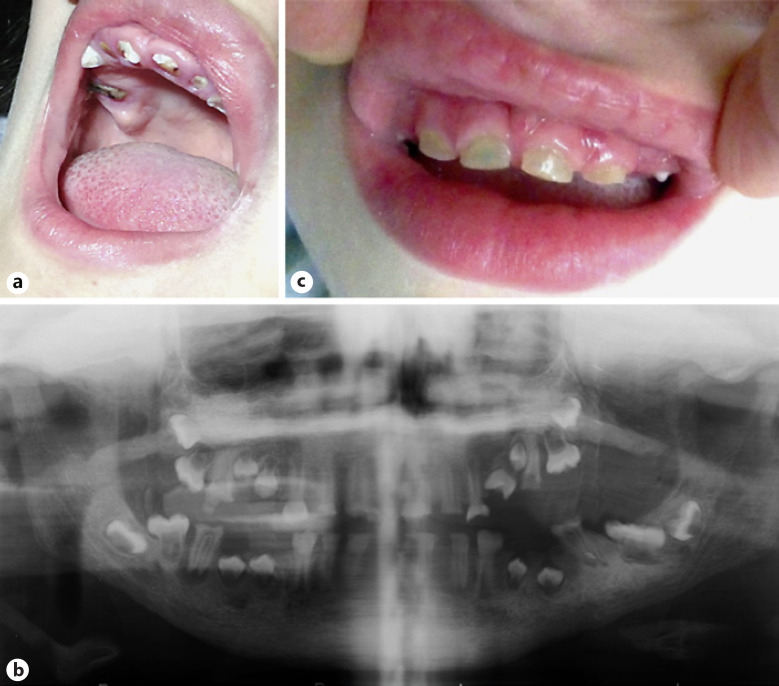

Fig. 3.

Images displaying the dental features of patient 1 (a), a panoramic X-ray of patient 1 (b), and the dental features of patient 2 (c).

We saw her when she was 12 years old. She had severe intellectual disability. Her height was 143 cm (15th centile), weight 44 kg (66th centile), and her head circumference (OFC) was 56 cm (95th centile). She had a flat forehead, sparse eyebrows and eyelashes, a broad nasal bridge, a telecanthus with palpebral fissures of 2.8 cm (Z-score = −1.28), inner canthal distance of 4.5 cm (Z-score = 1.88), outer canthal distance of 10.1 cm (Z-score = 0), an interpupillary distance of 7 cm (Z-score = 1.88), dysplastic, low-set ears, flat philtrum, thick lips, and a large mouth (Fig. 2a). Clinical oral examination revealed that all teeth in both dentitions were affected with generalized opalescent tooth discoloration (yellow-brown translucent), enamel frequently separates easily from dentin and wear of enamel that was flushed with the level of the gingiva (Fig. 3a). Radiographic examination based on a panoramic X-ray (Fig. 3b) showed bulbous crowns with cervical constriction, long tapered roots, and progressive obliteration of the pulp chamber.

Telecanthus was striking with palpebral fissures of 2.6 cm (Z-score = 1.65), inner canthal distance of 4.3 cm (Z-score = 1.88), and outer canthal distance of 9.9 cm (Z-score = 1.88). His hair, eyelashes and eyebrows were sparse; the nasal bridge broad; the philtrum flat; the upper lip thin; the lower lip everted, and the mouth large. There was a generalized opalescent tooth discoloration (blue-gray translucent). Teeth were also weaker than normal, making them prone to rapid wear, breakage, and loss, with abrasion and some coronal fracture (Fig. 3c). Radiographic examination based on an occlusal X-ray showed large pulp chambers in the primary dentition. The clinical and radiographic findings sustained a diagnosis of dentinogenesis imperfecta. Shoulders were narrow and sloping. Ophthalmological examination showed the presence of astigmatism. Heart ultrasound and electrocardiogram tests were normal.